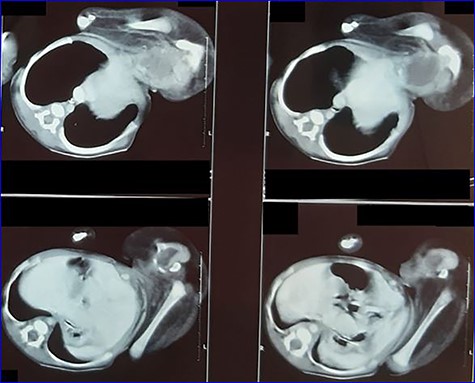

Contrast enhanced computed tomography (CT): (Figs 3 and 4)

No obvious anomalies in the autosite viscera. No clear vascular or visceral contact between the twins. The parasite consists of pelvic and two femur bones with cystic formation may represent a bladder. A single pelvic kidney is suspected with some intestinal loops in the pelvis.

Contrast-enhanced CT scan image showing parasite’s viscera and bony parts.